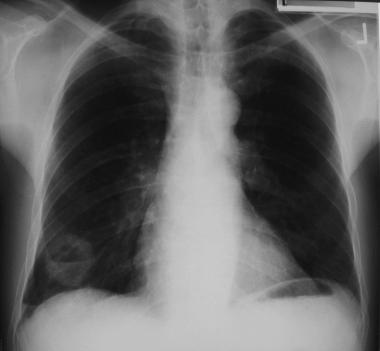

Первичным методом исследования обычно является рентгенография органов грудной клетки. При ней большая часть солитарных легочных очагов обнаруживаются случайно. В некоторых исследованиях изучалось использование низкодозовой КТ органов грудной клетки в качестве инструмента скрининга рака легкого; так, применение КТ приводит к обнаружению более мелких узлов, которым необходимо дать оценку. По мере увеличения доступности, важную роль в диагностике солитарных легочных очагов будут также играть ПЭТ и ОФЭКТ.

Рентгенография грудной клетки характеризуется лучшим разрешением по сравнению с КТ при определении степени выраженности обызвествления и его размеров. В то же время, визуализация некоторых легочных узлов может быть осложнена из-за наложений других органов и тканей.

Необходимо избегать ошибок интерпретации. Так, за опухолевый узел в легким можно ошибочно принять тени сосков, опухоли в мягких тканях грудной стенки, костные структуры, плевральные наложения, а также округлый ателектаз или участок воспалительной инфильтрации. Для снижения риска ошибки полезно заручиться вторым мнением.

Часто солитарные легочные узлы впервые обнаруживаются на рентгенограммах органов грудной клетки и являются случайной находкой. Первым вопросом, на который необходимо ответить, располагается ли обнаруженный очаг в легком или находится вне его. С целью уточнения локализации изменений выполняется рентгенография в боковой проекции, рентгеноскопия, КТ. Обычно узлы становится различимыми на рентгенограммах, когда достигают размера 8–10 мм. Иногда могут обнаруживаться узлы размером 5 мм. На рентгенограммах можно определить размер очага, темпы его роста, характер краев, наличие обызвествлений – изменения, которые могут помочь оценить выявленный узел как доброкачественный или злокачественный.